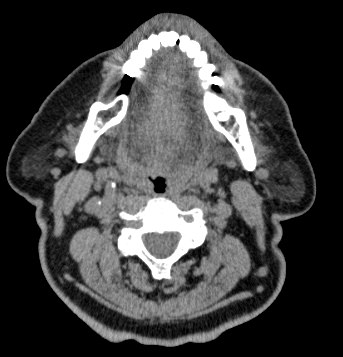

Мультиспиральная компьютерная томография – это высокоинформативный лучевой метод диагностики различной патологии мягких тканей шеи, включая воспалительные заболевания, травматические повреждения и опухолевые процессы. КТ позволяет оценить состояние щитовидной железы, паращитовидных желез, гортани, верхней части пищевода, шейных лимфоузлов и окружающих мягких тканей.

Метод КТ основан на применении рентгеновского излучения. Однако в отличие от обычного рентгена, при котором снимки производятся в одной плоскости, при КТ излучатель рентгеновских лучей постоянно двигается вокруг объекта исследования, проводя сканирование в различных плоскостях, а затем трансформируя полученные данные в цифровые трехмерные изображения. Это дает возможность визуализировать органы и ткани в мельчайших подробностях, а с помощью объемных 3D-реконструкций наглядно оценить пространственное расположение органов и патологических образований.

Рентгеновские лучи лучше всего поглощаются плотными структурами, такими как костная ткань. Поэтому кости хорошо видны на снимках КТ. Это делает компьютерную томографию незаменимой при необходимости обследования, в частности, костного скелета гортани. Однако для улучшения визуализации мягких тканей требуется введение специального контрастного препарата, поэтому КТ мягких тканей шеи в подавляющем большинстве случаев проводится с контрастным усилением.

Для контрастирования используется йодсодержащее контрастное вещество, которое в составе рентгеноконтрастного препарата вводится в вену пациенту непосредственно во время исследования. Благодаря способности контраста поглощать рентгеновские лучи на снимках КТ хорошо контрастируются кровеносные сосуды и опухолевые образования, имеющие, как правило, развитую сосудистую сеть. Методика внутривенного болюсного контрастирования помогает обнаружить воспалительные изменения, отличить доброкачественные опухоли от злокачественных, выявить поражение лимфатических узлов и степень прорастания опухоли в магистральные сосуды и окружающие ткани.